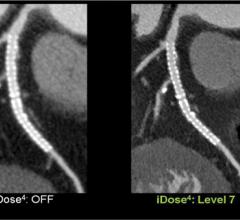

Radiation exposure from multidetector computed tomography (CT) has become a pressing public health concern in both lay and medical publications. Implementation of iterative reconstruction offers the ability to minimize radiation exposure while preserving and, in some cases, improving image quality. However, in order to evaluate iterative reconstruction software, one must first understand the basics of how it works.

New computed tomography (CT) dose studies and growing public media attention have made minimizing unnecessary radiation dose to patients a priority for medical imaging facilities. In addition, state regulatory agencies and accrediting bodies are increasing their oversight and regulation of radiation dose. Reducing dose while maintaining good clinical image quality, however, is complex.